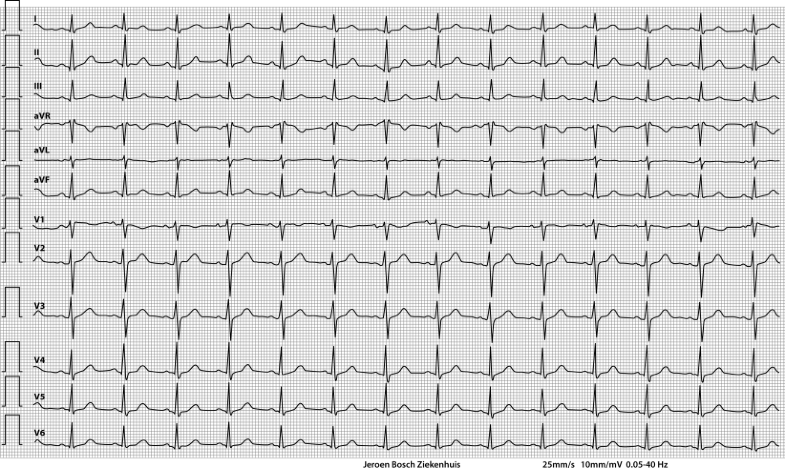

Follow-up ECG after discharge from the intensive care unit

Type 1 Brugada-like ECG pattern provoked by TCA intoxication.